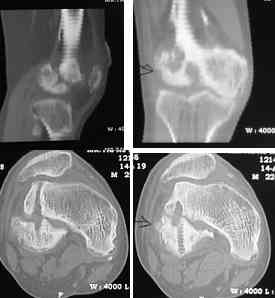

I opened it up from the lateral aspect.

Freed up the non-union site with minimal disturbance to the posterior and lateral soft tissue attachments on the lateral condyle fragment.

Applied a distractor between femoral shaft and tibia, to create a space on the lateral aspect.

This brought the lateral condylar fragment into a position that seemed to be reasonably well aligned, but showed up a bone gap.

This was fixed temporarily, bone grafted with tricortical struts, and fixed by two cancellous screws. The fragment was not large enough to afford any fixation to a plate or such implant, and the screws held it compressed well to the rest of the distal femur.

Post-op - limb is well aligned, rom 0-30, but I am not pushing that right now, for the next two or three weeks.

Further plan - hope that the screws hold the fragment appropriately till union, but if the stability on table is anything to judge by, that should not be a problem.

Quadricepsplasty after a year or so, to restore flexion.

Pictures attached.